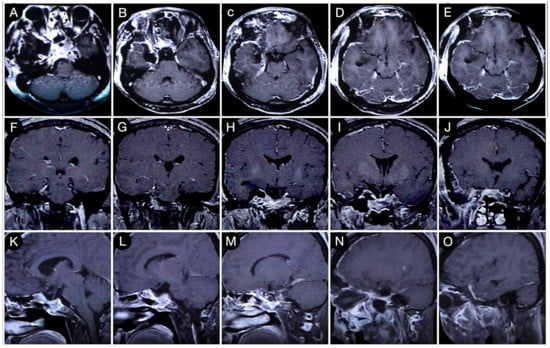

Case #1: Infradiaphragmantic Tumor with Middle Fossa Involvement through the Cavernous Sinus

3.2.1. Case #2: Involvement of the Anterior Skull Base

3.2.2. Case #3: Paramedian Pattern of Growth with Parenchymal Invasion

3.3.1. Case #4: Involvement of the Middle Skull Base with Parenchymal Invasion

3.3.2. Case #5: Extension beyond the Lateral Wall of the Cavernous Sinus

3.3.3. Case #6: Encasement of the Posterior Communicating and Anterior Choroidal Artery

Case #7: Encasement of the Paraclinoid and Supraclinoid Internal Carotid Artery

Case #8: Aggressive ACTH Tumor with Multiple Recurrences